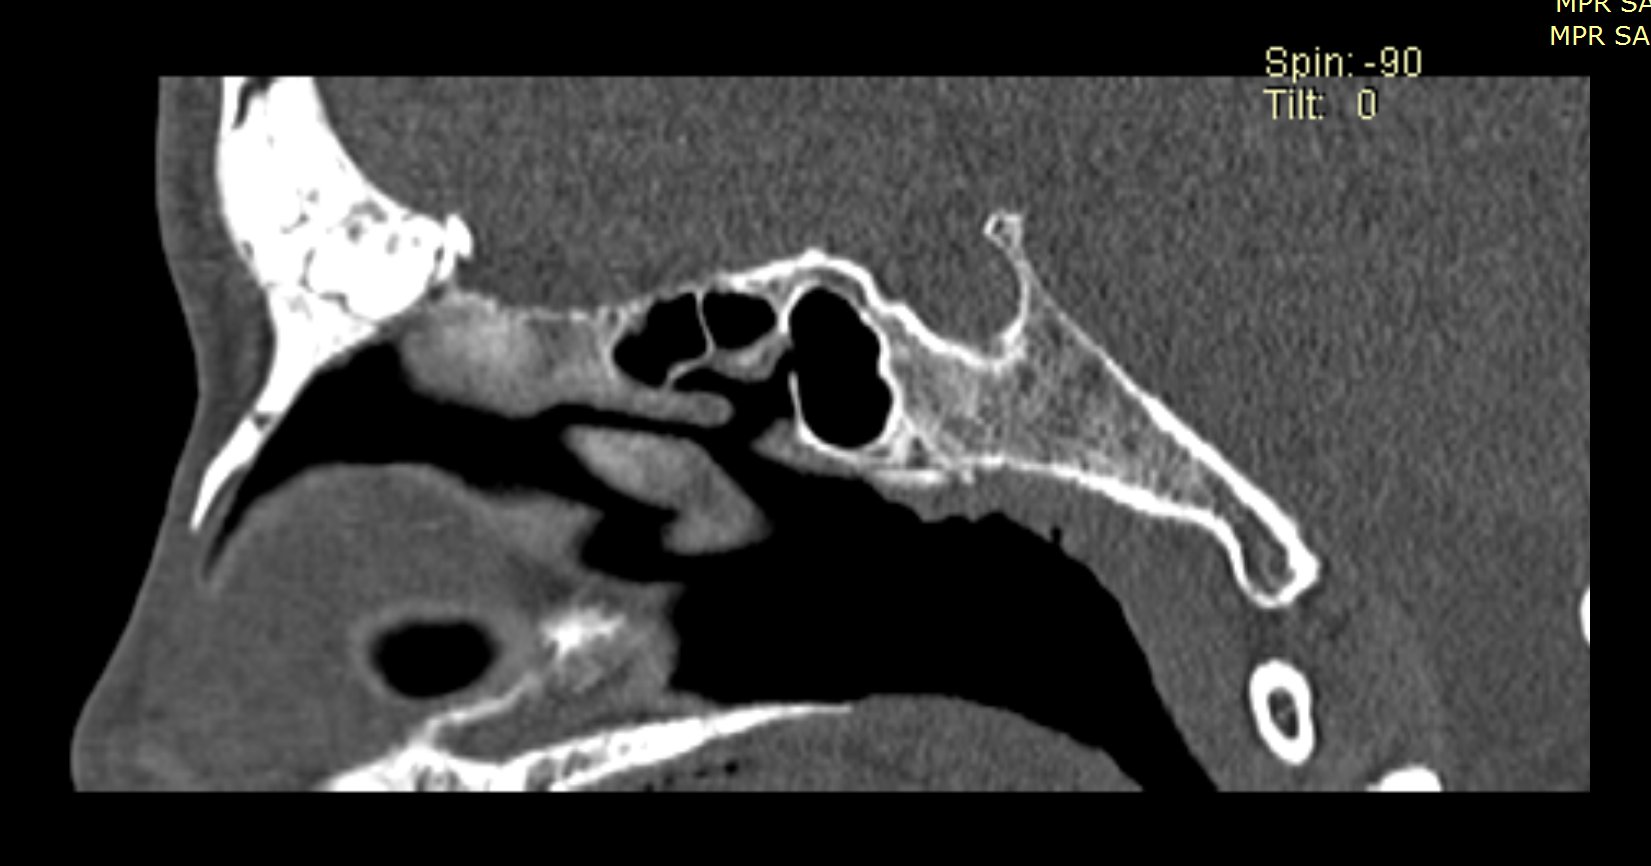

Examenul clinic ORL și examenele imagistice complementare (CT, RMN sinusuri paranazale) pun în evidență o formațiune tumorală osteogenică a sinusului frontal drept, protruzivă în unghiul supero-intern al orbitei, extinsă medial către sinusul frontal stâng.

- Se expune formațiunea tumorală osteomatoasă care ocupă în totalitate cavitatea sinusală frontală dreaptă, se extinde către sinusul frontal controlateral și către orbita dreaptă, creând presiune pe atmosfera celulo-grasoasă periorbitară la nivelul unghiului supero-intern OD. Formațiunea este intens aderentă la nivelul peretelui sinusal postero-superior. Aceasta prezintă două zone de consistență diferită.